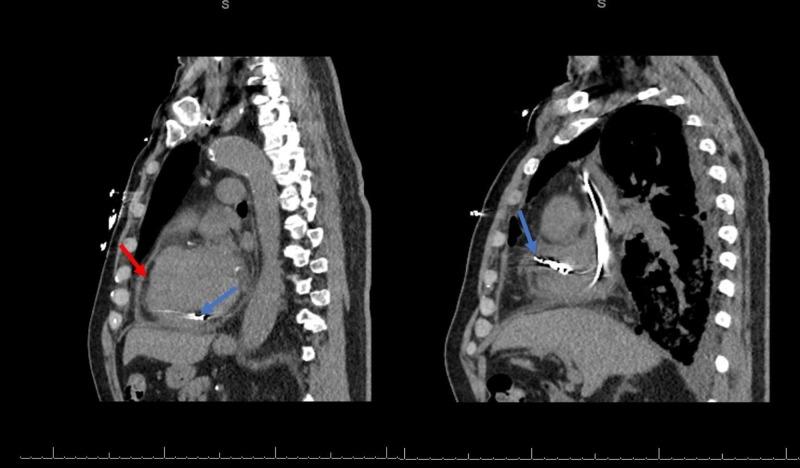

Post-cardiac injury syndrome (PCIS) as a delayed complication of permanent pacemaker implantation has rarely been reported in the literature. A 67-year-old man who recently underwent a dual chamber permanent pacemaker implantation came to the hospital for increasing dyspnea and chest discomfort. A diagnosis of pericarditis was made, and the patient was discharged on ibuprofen therapy. He presented to our facility a month later with worsening dyspnea and chest discomfort despite recommended therapy. A computerized tomography (CT) scan of the chest revealed a large right-sided pleural effusion, requiring chest tube placement and drainage. A pleural fluid analysis revealed exudative effusion with elevated pH. The pleural fluid analysis was negative for infectious etiology. A perforation of the atrial wall was considered given the proximity of the atrial pacer lead and overlying pericardial effusion. However, no conclusive evidence of cardiac chamber perforation was found on echocardiogram or CT scan. A pacemaker interrogation was normal. A repeat CT scan showed the resolution of pleural effusion, and the chest tube was discontinued. A possible explanation for the absence of predominant pericardial findings may be the previous use of non-steroidal anti-inflammatory therapy.

心脏损伤后综合征(PCIS)作为永久性起搏器植入的延迟并发症,在文献中鲜有报道。一名67岁男性近期接受了双腔永久性起搏器植入术,因呼吸困难加重和胸部不适前来医院就诊。诊断为心包炎,患者出院时接受布洛芬治疗。尽管接受了推荐治疗,但一个月后他因呼吸困难和胸部不适加重再次来到我们的机构。胸部计算机断层扫描(CT)显示右侧大量胸腔积液,需要放置胸管引流。胸腔积液分析显示为渗出性积液,pH值升高。胸腔积液分析未发现感染性病因。考虑到心房起搏器导线靠近且存在心包积液,怀疑心房壁穿孔。然而,超声心动图或CT扫描均未发现心腔穿孔的确切证据。起搏器程控检查正常。重复CT扫描显示胸腔积液消退,胸管拔除。心包主要表现不明显的一个可能解释是先前使用了非甾体抗炎治疗。